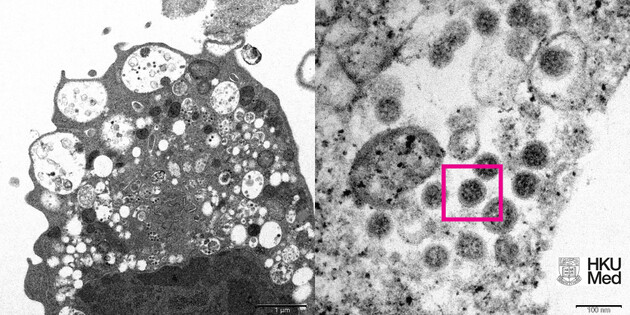

Дві дози китайської протиковідної вакцини Coronavac не дають достатнього захисту від штаму «Омікрон». Про це повідомили вчені з Гонконгу, оприлюднивши своє дослідження на сайті препринтів Medrxiv.

Науковці зазначили, що Coronavac не дає достатньо антитіл, щоб запобігти зараженню «Омікроном». Вони дослідили імунну відповідь на зразках крові 25 людей, що пройшли повний курс імунізації. Вчені доповнили, що зразок не виробив достатньо антитіл, щоб заблокувати «Омікрону» вхід у клітини людини.